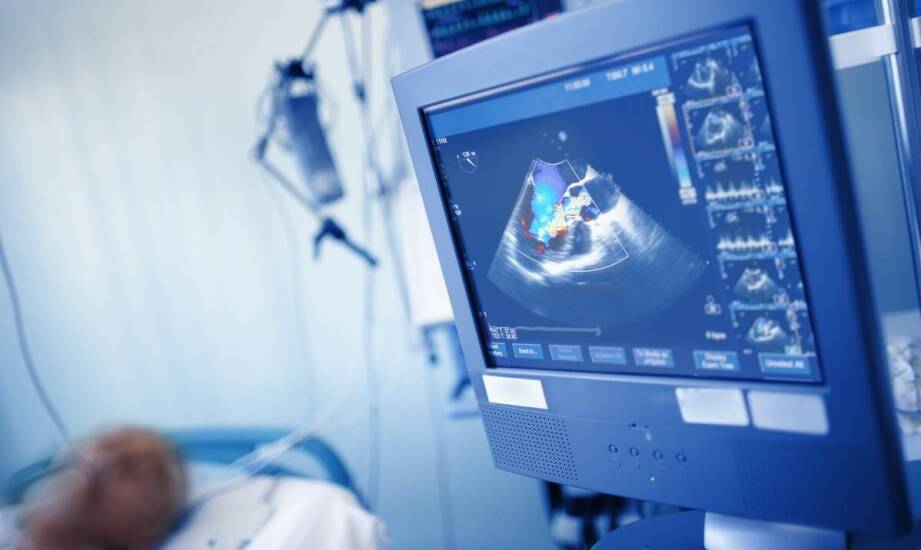

Doppler USG to narzędzie w kardiologii, które służy do oceny stanu pacjentów z problemami sercowo-naczyniowymi. W Specjalistycznej Praktyce Lekarskiej Elizy Majczyńskiej lekarze we Włocławku mogą ocenić przepływ krwi oraz funkcje serca, co jest istotne u osób z chorobami tego organu. Metoda ta jest nieinwazyjna, co zwiększa komfort pacjentów i umożliwia wykonywanie badań kontrolnych. Wykorzystanie Doppler USG w praktyce klinicznej może mieć znaczenie dla diagnostyki i monitorowania terapii w kardiologii, a także wpływać na jakość opieki nad chorymi.

USG Doppler we Włocławku oraz innych miejscowościach umożliwia analizę przepływu krwi w sercu oraz naczyniach krwionośnych. Technologia ta pozwala na identyfikację nieprawidłowości, takich jak zwężenia czy niedrożności, które mogą wiązać się z powikłaniami zdrowotnymi. Wczesne wykrywanie problemów kardiologicznych jest ważne dla dalszego postępowania diagnostycznego i leczenia. USG Doppler odgrywa istotną rolę w monitorowaniu stanu zdrowia pacjentów z chorobami serca, umożliwiając ocenę stosowanej terapii oraz dostosowanie jej do potrzeb chorego. Specjaliści mogą podejmować decyzje dotyczące dalszego leczenia. Włocławek i inne miejscowości oferują dostęp do metod diagnostycznych, takich jak USG Doppler we Włocławku, które są przydatne w kontekście chorób układu krążenia. Regularne badania mogą stanowić element kontroli stanu serca i naczyń krwionośnych oraz pomagać w ocenie ryzyka wystąpienia problemów zdrowotnych. Dzięki tym badaniom możliwe jest wczesne wykrycie nieprawidłowości, co może wpływać na jakość życia pacjentów. Wyniki badania są oceniane w odniesieniu do objawów i innych informacji klinicznych.